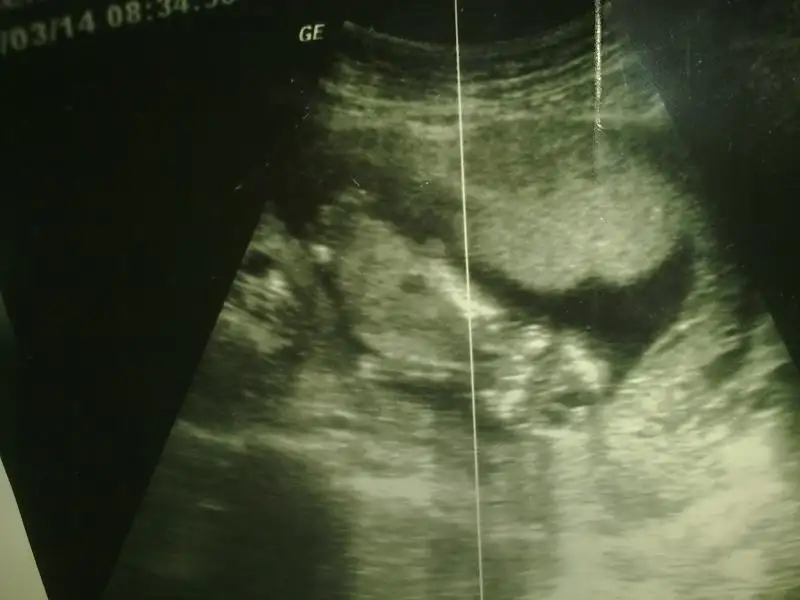

Gurbet ablam arkadasimin bebegi ALLA RIZASI ICIN BI BAKSAN KIZ MI ERKE MI? ustteki iki resim bugunku goruntuler en alttaki 6 hatalikken

Kilar bilen varsa bi baksin nolur cok yakinimin bebegi stres altinda biraz en azindan ne oldugunu biliyim kendimife kocamid alistiriyim diyo